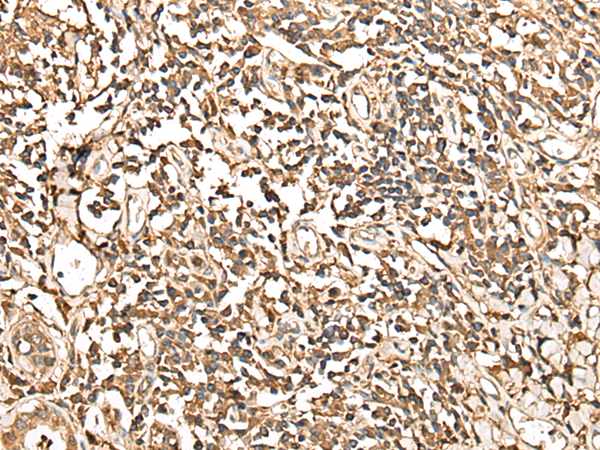

分类: 科研抗体货号: P02461别名: CALC; EFHA3; MPXPS; CBARA1应用: IHC反应种属: Human, Mouse, Rat